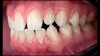

(5. and 6.) Side-by-side comparison of a contemporary smartphone camera image and a DSLR camera system image.

For most dental clinicians and technicians, the acquisition of professional-level photographs with a DSLR camera requires a steep economic investment and possesses a shallow learning curve. The time commitment and nebulous return on investment are certainly potent deterrents to the incorporation of these systems into daily practice. While remaining cognizant of the need for photographic documentation, the dental field has witnessed an increase at the low end of the dental photography continuum through the use of the ubiquitous smartphone as a proxy for the larger and more expensive DSLR camera setups. Most smartphones will allow the user to customize and control the elements of the exposure triangle via the internal camera settings or by means of a third-party application (Figure 4); however, the diminutive nature of the lenses, apertures, and sensors of these devices makes the necessary attainment of light problematic. When this is coupled with low-capacity native light output on the subject being photographed, the resulting images are often distorted, low-resolution, and possess inconsistent reproduction of color and detail, which renders them unacceptable for documenting patient treatment and collaborating with the laboratory (Figure 5 and Figure 6).